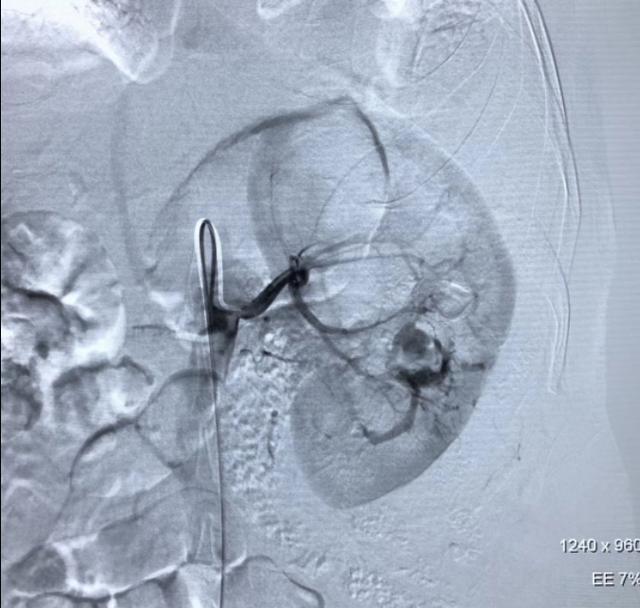

术中造影发现左肾正常形态消失,发现多处血管破裂并伴有造影剂迅速外溢,还在出血,病情非常凶险。夏风飞医生与张主任配合默契,立即应用微导管逐一的对靶向分支血管进行选择造影,查找可能的出血点。采用不同角度,对肾动脉各个分支分别重复造影,术*共中**发现了4条出血血管,在尽量保护仅存的左肾良好组织的前提下,应用微弹圈进行了精确栓塞微创止血治疗。